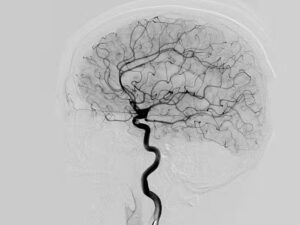

The new doctor listens to my medical history and family history and says, we should bet an MRA of your brain since you have two family members with intracranial aneurysms and subarachnoid hemorrhages. I had gotten an MRI/MRA 24 years ago – on the fly, off-book- while my sister lay in the ICU after her craniotomy. Normal and negative they said. Great!

Except they missed it. It was there. All this time. Through all the stress and pressure and fear and worry. There was an aneurysm. It was there when I divorced. It was there when I fell in love. It was there when I remarried. It’s just been sitting there, slowly growing. The new MRA clearly shows it. 6.4mm just inside the dural ring off the left internal carotid. In the intervening 20+ years it nearly doubled in size and has a daughter cell (the aneurysm has an aneurysm). And now I have to “do something”.